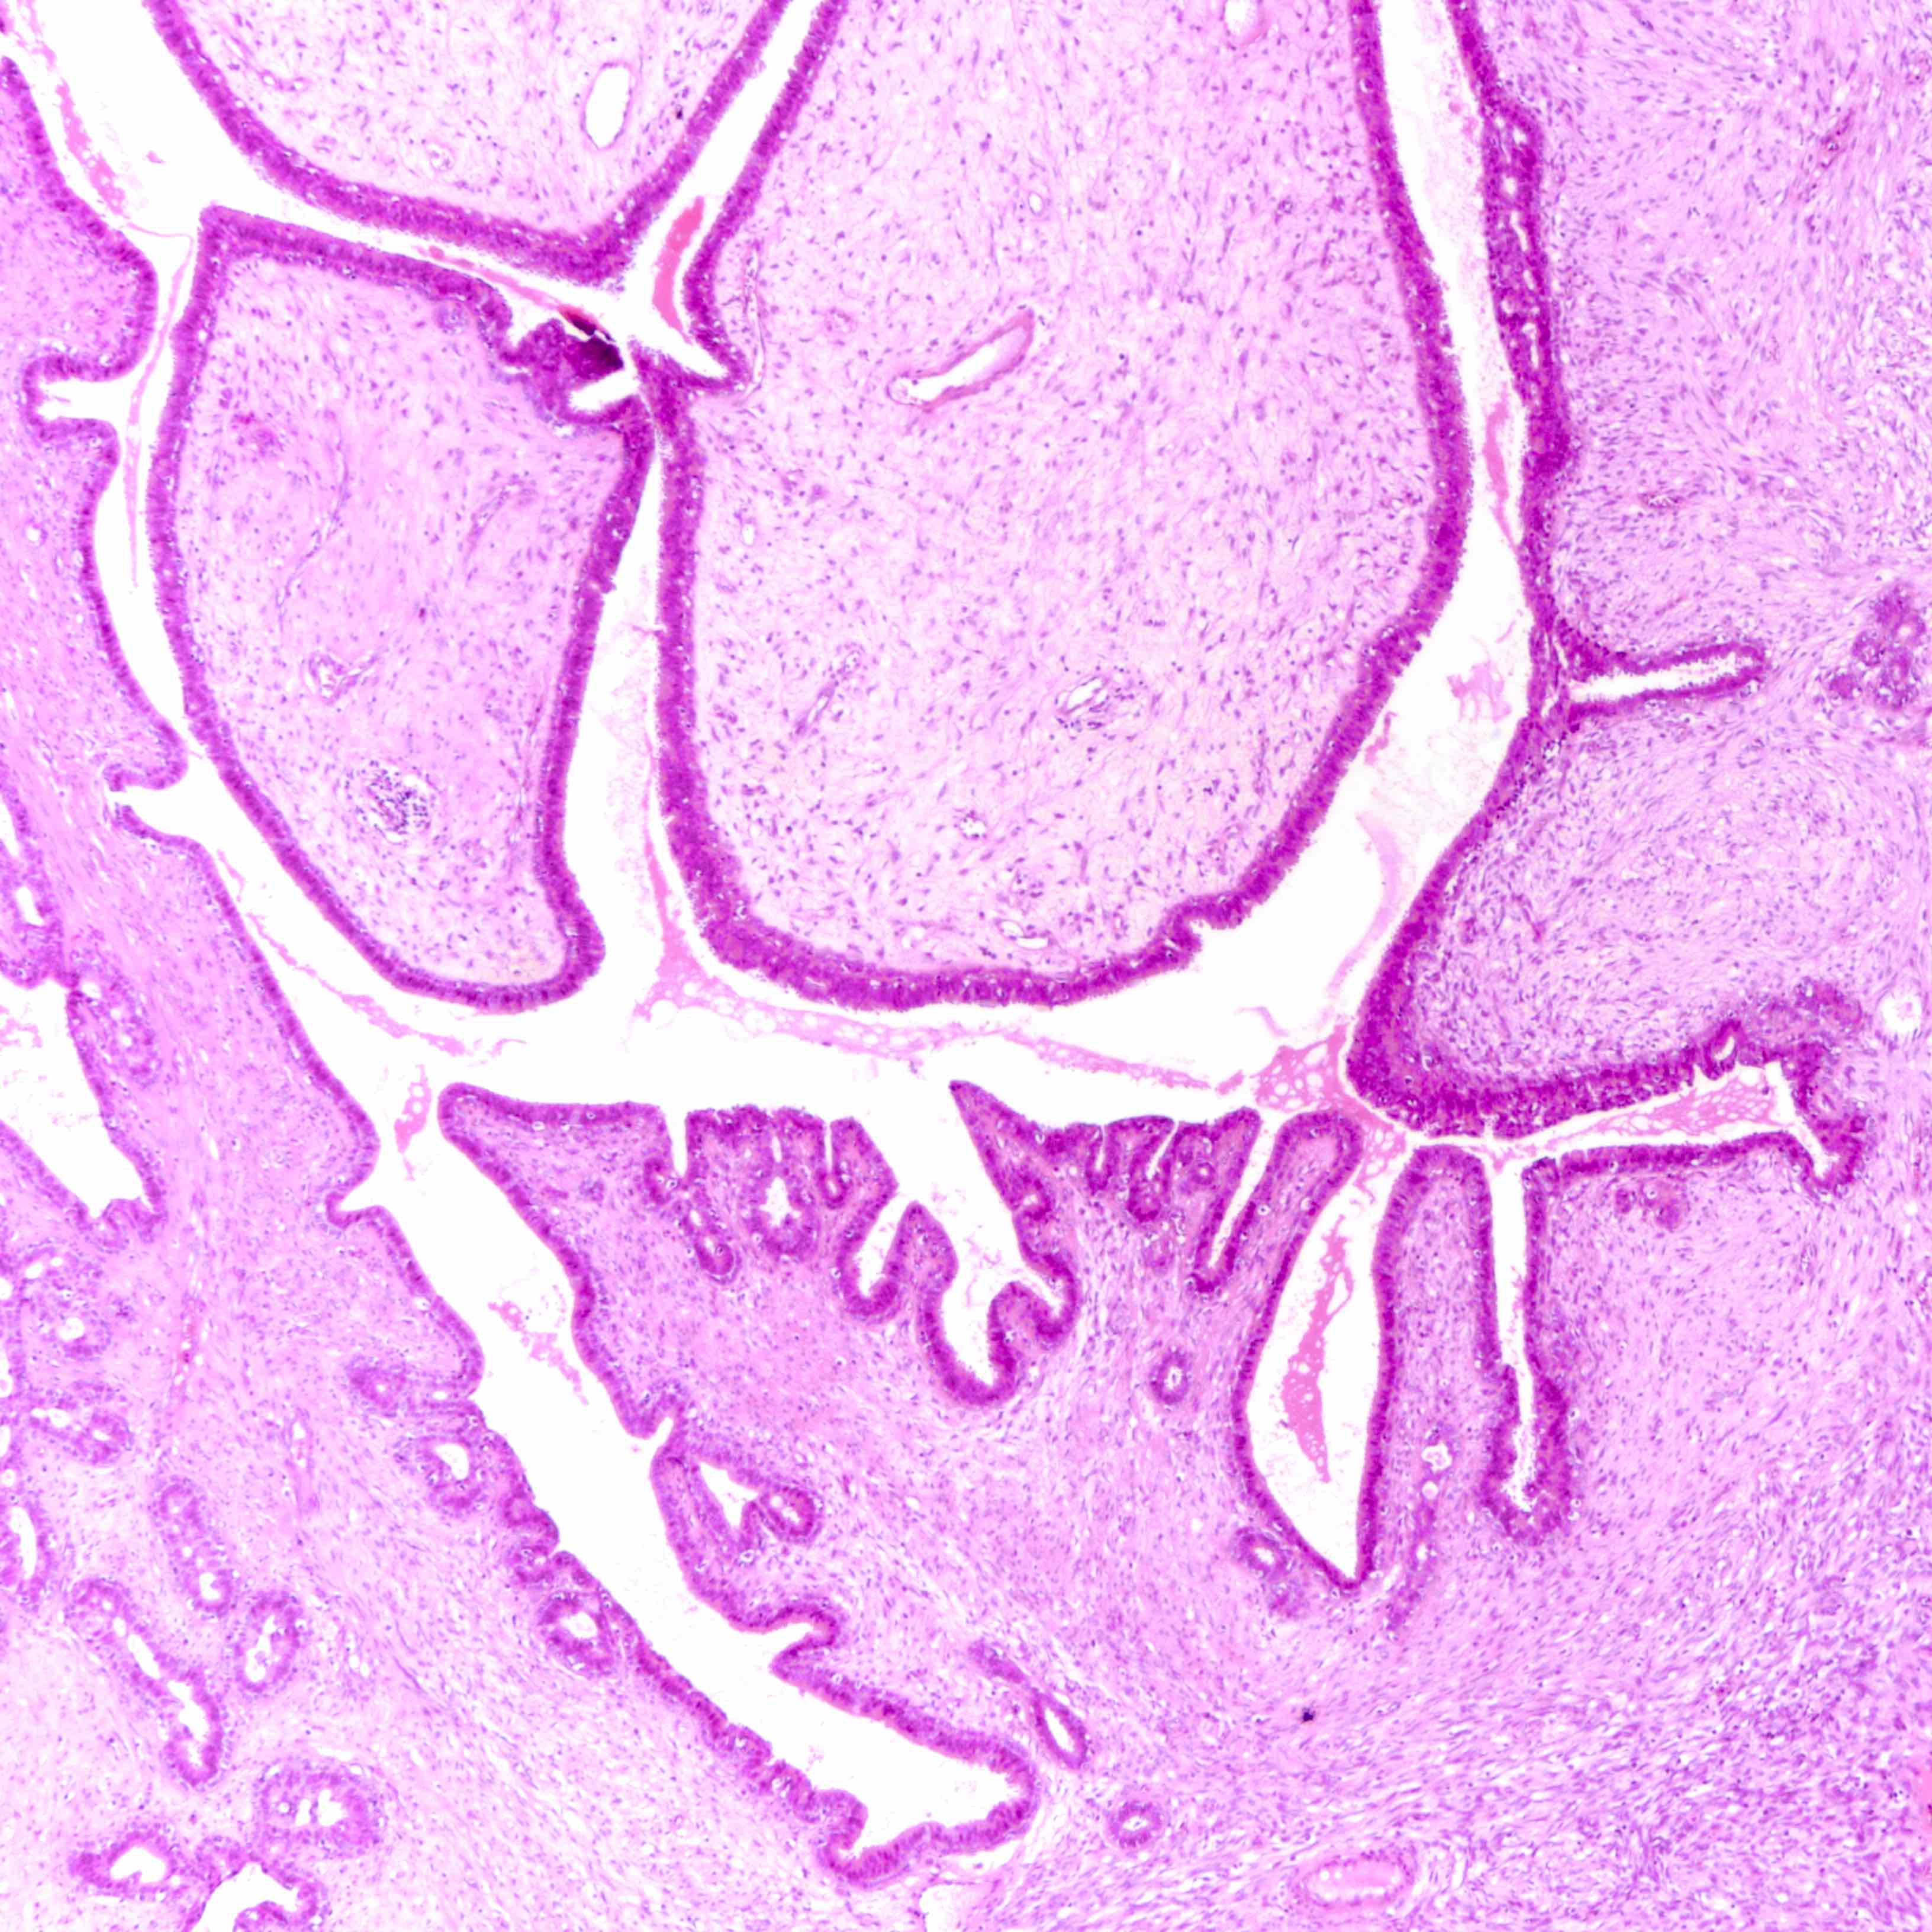

Microscopic (histologic) images

Contributed by Joshua J.X. Li, M.B.Ch.B. and Gary M. Tse, M.B.B.S.

Benign phyllodes tumor

Borderline phyllodes tumor